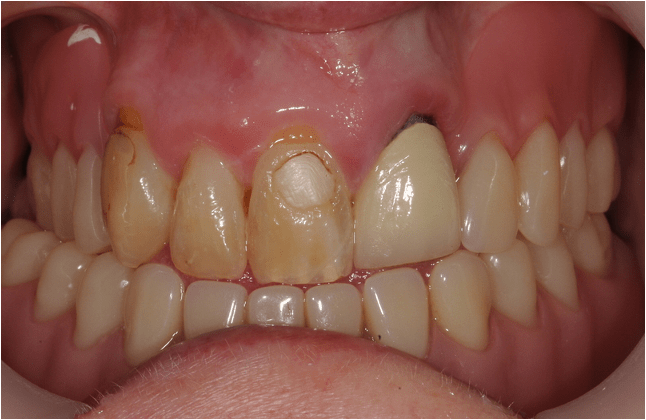

Crowns

Crowns may be used to treat toothwear or broken down teeth. They are often selected where composite has failed, the teeth are too broken down or there is a need to provide a stronger material. This case was managed with surgical crown lengthening and multiple crowns. The lower incisors were treated with composite.